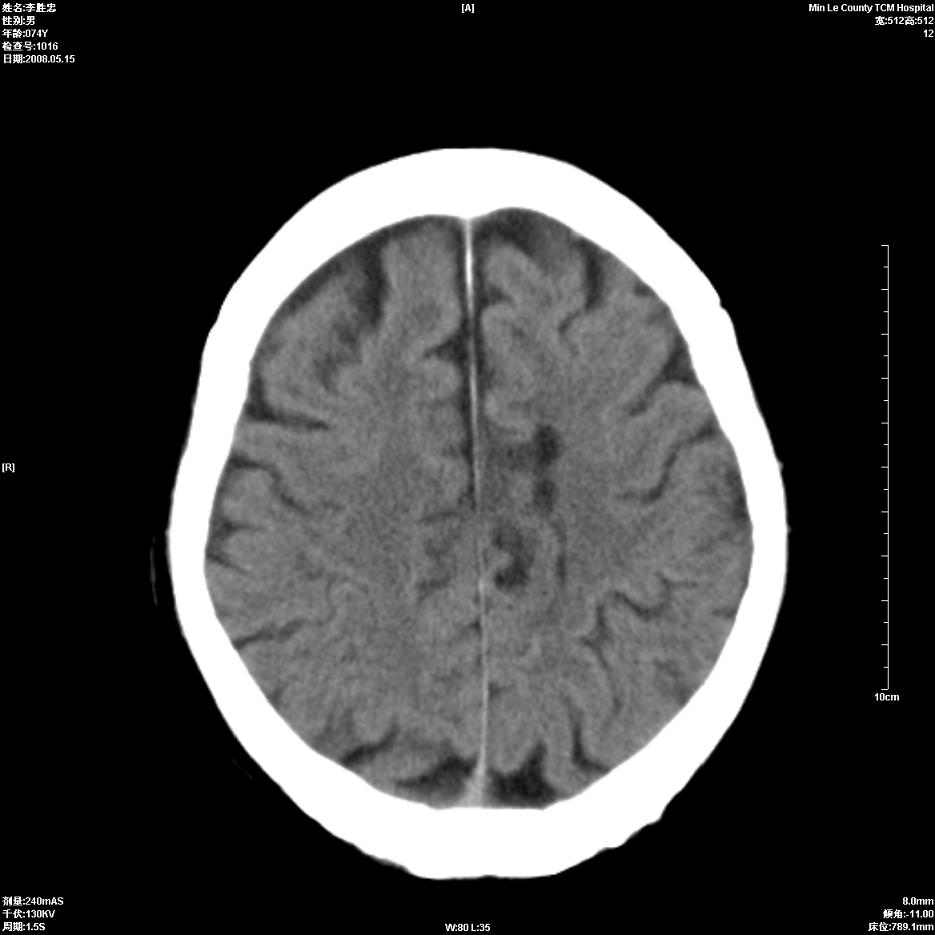

以下是引用hhcckk在2008-5-30 14:26:00的发言:[br]病灶跨中线,有占位效应,强化不明显,考虑胼胝体区低级别的星形细胞瘤可能性大,建议mr检查